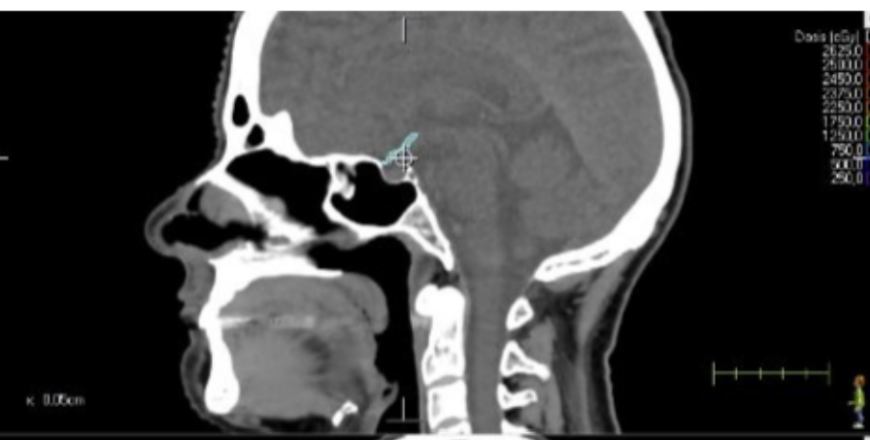

Sistema Nervioso Central